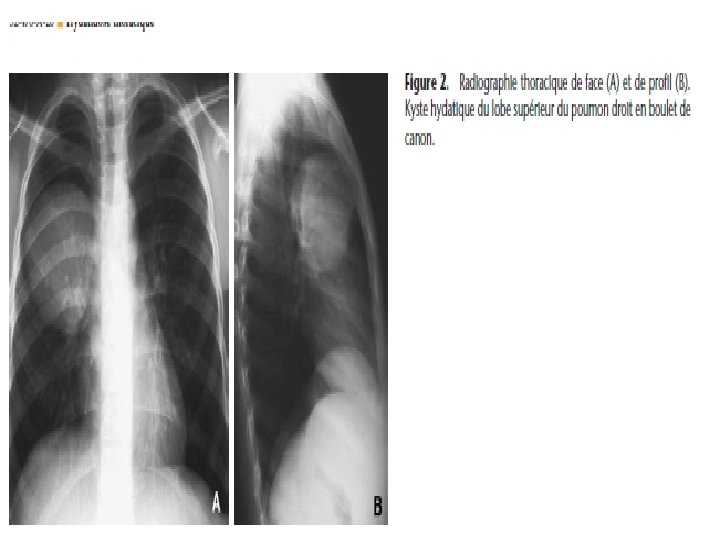

Kyste hydatique du poumon • Evolution radio-clinique 06 stades successifs: 1) Kyste sain. Asymptomatique de découverte fortuite (stade exclusivement radiologique)= opacité ronde, nettement limitée, en « boulet de canon » , dans un parenchyme sain, profil, opacité ovalaire « en ballon de rugby » , signe de NEMENOFF en radioscopie

Imagerie médicale